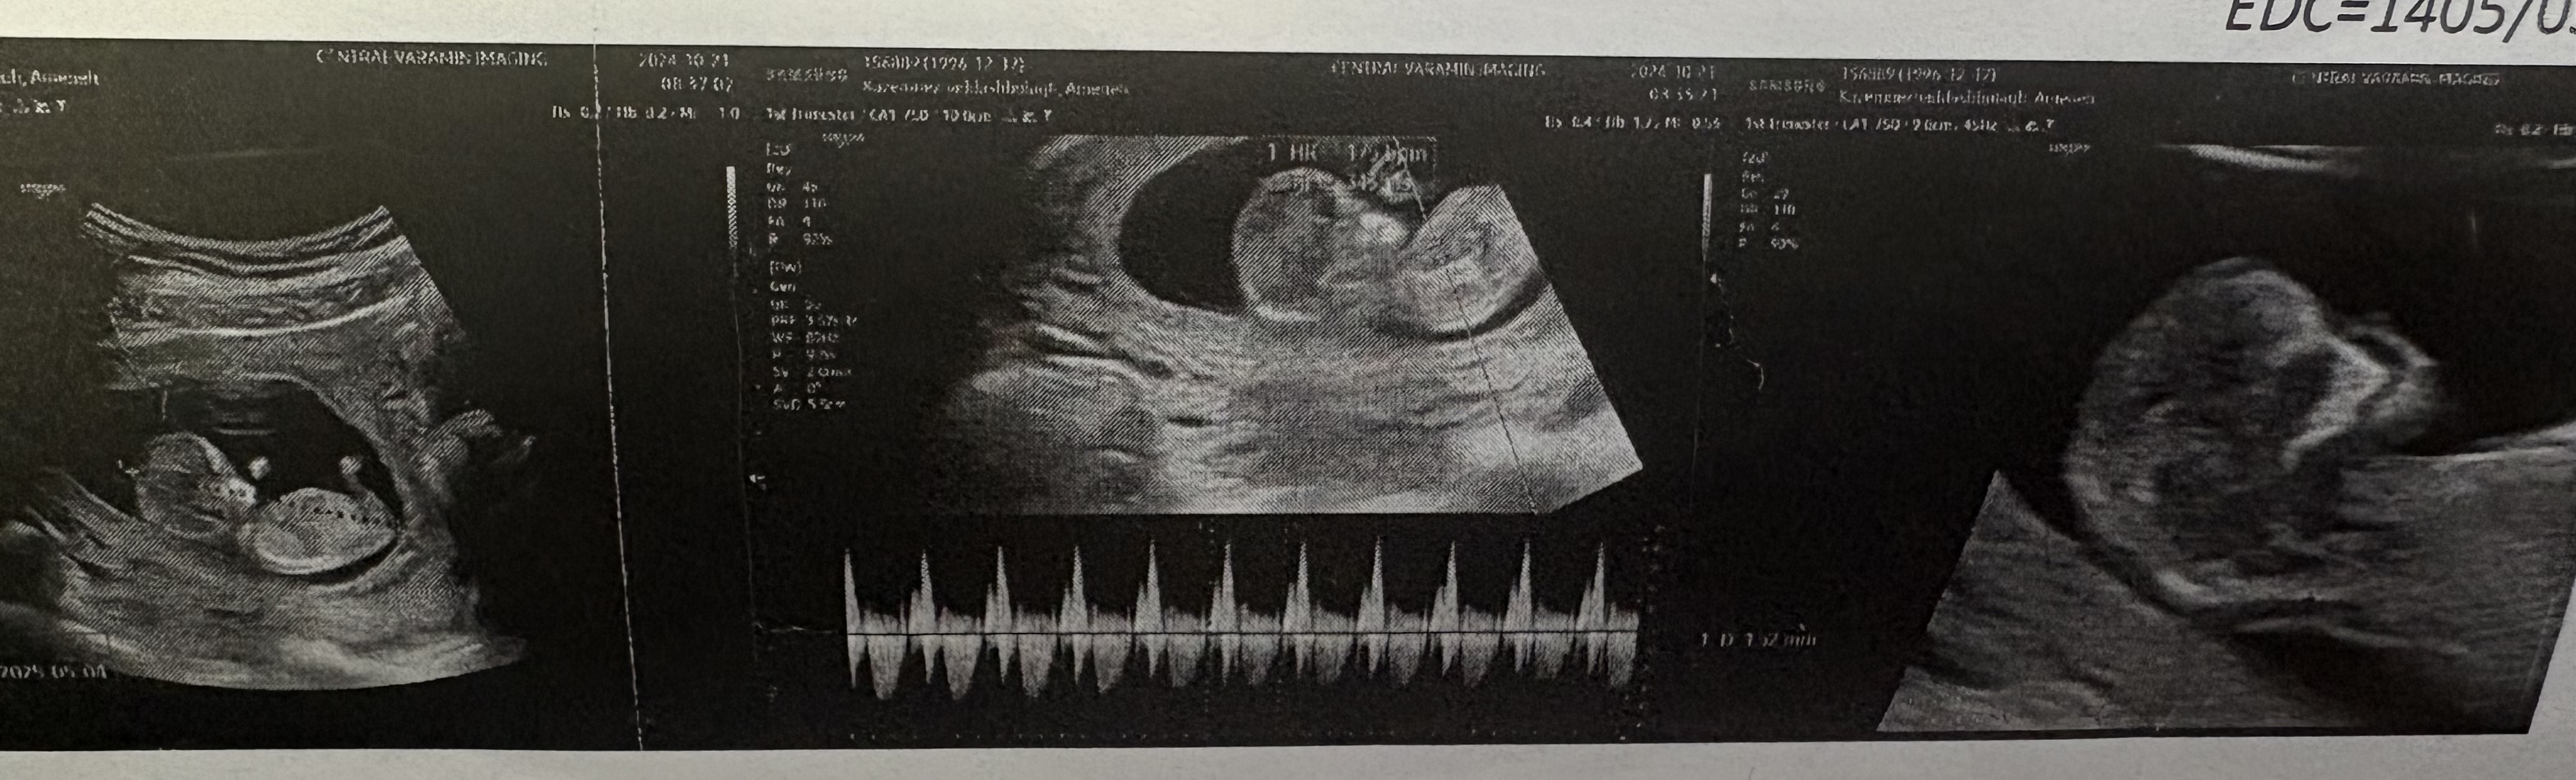

دلوین۷۵ مدیر استارتر عضویت: 1401/08/24 تعداد پست: 1997 عنوان عکس سونو nt 327 بازدید | 44 پست میشه بیاید قبلا هم تاپیک زدن کسی نیومد دکتر سونو نفهمید جنسیت بچمو 1404/11/10 | 15:14 0 نفر لایک کرده اند ... گزارش تاپیک نامناسب

دلوین۷۵ مدیر استارتر عضویت: 1401/08/24 تعداد پست: 1997 عزیزم دکتر نفهمیده ما از کجا بفهمیم بگی نهایت همینجوری شانسی نظر بدیم دورهم آخه تو تاپیکا دیدم بعضیا از فرم جمجمه تشخیص میدن حالا حستون هم بگید خوبه ممنون میشم

دلوین۷۵ مدیر استارتر عضویت: 1401/08/24 تعداد پست: 1997 اره ولی الکیه تنها قسمت تناسلی باید دکتر ببینه بگهالان ممکنه چند نفر بگن پسره چند نفر بگن دخترههفته ... من ۱۲ هفته و ۱ روز رفتم نفهمید

دلوین۷۵ مدیر استارتر عضویت: 1401/08/24 تعداد پست: 1997 دکتر سونو که تخصصشه نفهمیده ، کاربرای اینجا هم نمیدونن آخه دیدم تو تاپیکا بعضیا مثلا از فرم جمجه میگن جنسیت چیه